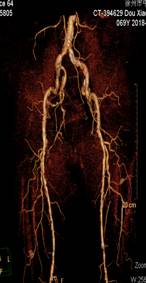

窦××,男,79岁,“右足部疼痛伴局部破溃半年”入院,间歇性跛行200米,右踝关节局部1.5×1.5cm2溃疡,第5趾底1.0×1.0 cm2溃疡,表面渗出物。糖尿病病史23年,高血压病史23年,脑梗塞病史7年。下肢动脉CTA示双下肢动脉广泛斑块形成,多发狭窄,双侧膝下动脉间断显示,大部闭塞。经药物治疗10天,疼痛消失,可自行持续行走1000米以上双下肢无不适,原足趾部溃疡愈合,踝关节部溃疡结痂。